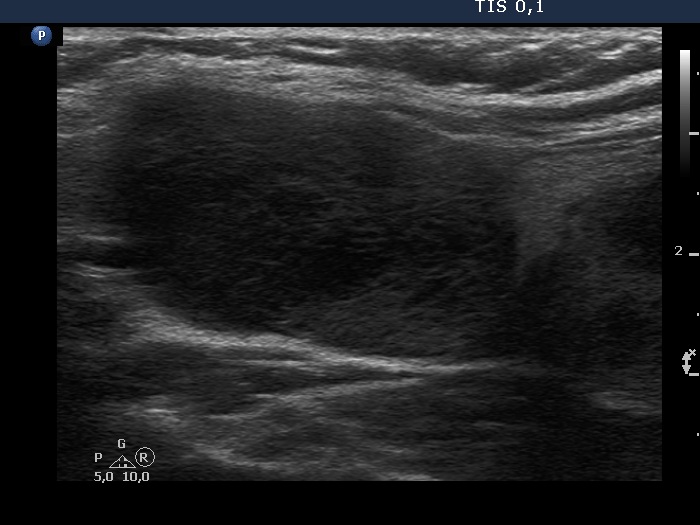

Second examination 3 years later (second, fourth and sixth rows of images):

Ultrasonography. Compared with the previous examination, both the number and the size of discrete lesions in the thyroid have increased.